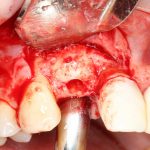

Кстати, обрати внимание на ширину альвеолярного гребня (левая картинка). Она чуть меньше 3 мм. Это объясняет, почему я засомневался в возможности установки имплантатов одновременно с остеопластикой. Понятно и без КЛКТ.

Наперво, мне нужно удалить разрушенный зуб и получить костный аутотрансплантат.

Возвращаемся к основной операционной области. Еще раз посмотрим на альвеолярный гребень, поофигеваем от его ширины и моих грандиозных планов: